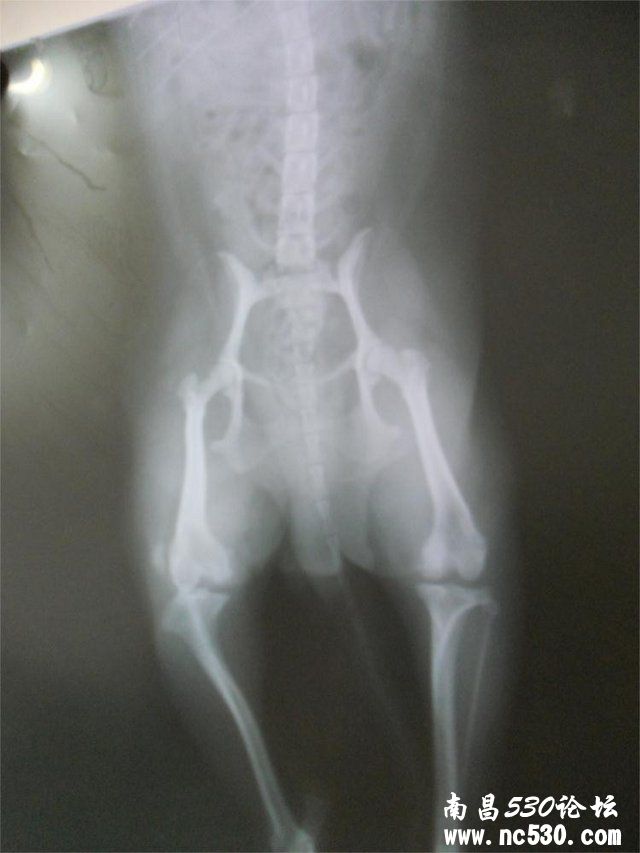

您好,这是我家两岁小泰迪的后腿腿骨片子,请问这是什么病症呢?现在这种情况严重吗?她长时间不动一起来腿就一瘸一拐的,走一会儿又好了。平时也不让她只用后腿站立。如果保守治疗的话应该注意些什么呢?平时还有什么要注意的呢?非常感谢您能在百忙之中给予帮助!

尽快考虑手术治疗  保守治疗只能缓解  不能起到根治       这种手术泰迪很常见